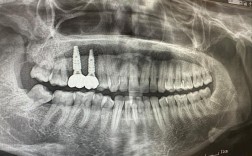

种牙手术的核心步骤包括切开牙龈、分离黏骨膜、制备种植窝、植入种植体、缝合伤口等,但现代局部麻醉技术已能让术中疼痛感降至最低——医生会在手术区域注射局麻药(如利多卡因),药物起效后(约1-2分钟),牙龈、牙槽骨等组织会失去知觉,患者通常只能感受到轻微的压力感或震动感,而非疼痛,制备种植窝时高速手机的震动、植入种植体时的轻微推挤感,都属于“非痛性刺激”,多数人都能轻松耐受。

手术时长因情况而异:单颗牙种植通常需30-60分钟,多颗或复杂病例(如需要植骨、上颌窦提升)可能延长至1-2小时,由于麻醉持续作用,整个过程中患者始终保持清醒,但不会感到疼痛,少数敏感体质者可能在麻药即将消退时感到轻微不适,但医生会提前判断,在必要时补充麻醉,确保手术结束前仍处于无痛状态。